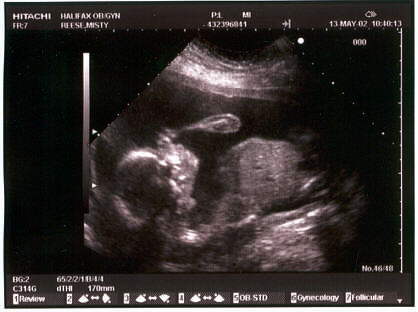

The ultrasound pictures (in May at 21 weeks):

A close up of our little girl to embarass her later.

A profile shot of the head at left and body right.